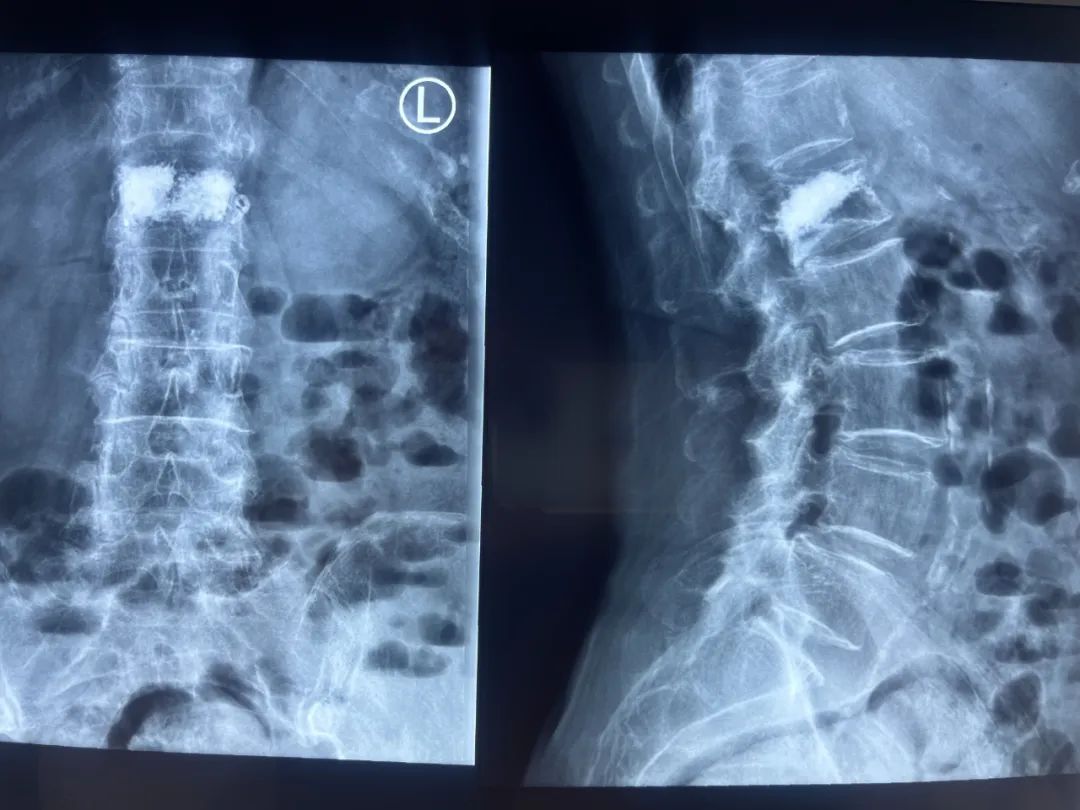

術前(qian)影像及診斷

DR及CT檢查

L1椎(zhui)體成形術(shu)后,L4椎(zhui)體向前I°滑脫。

L4/L5椎(zhui)間盤(pan)膨出并右(you)后(hou)突。

L5/S1椎間盤膨出(chu)。